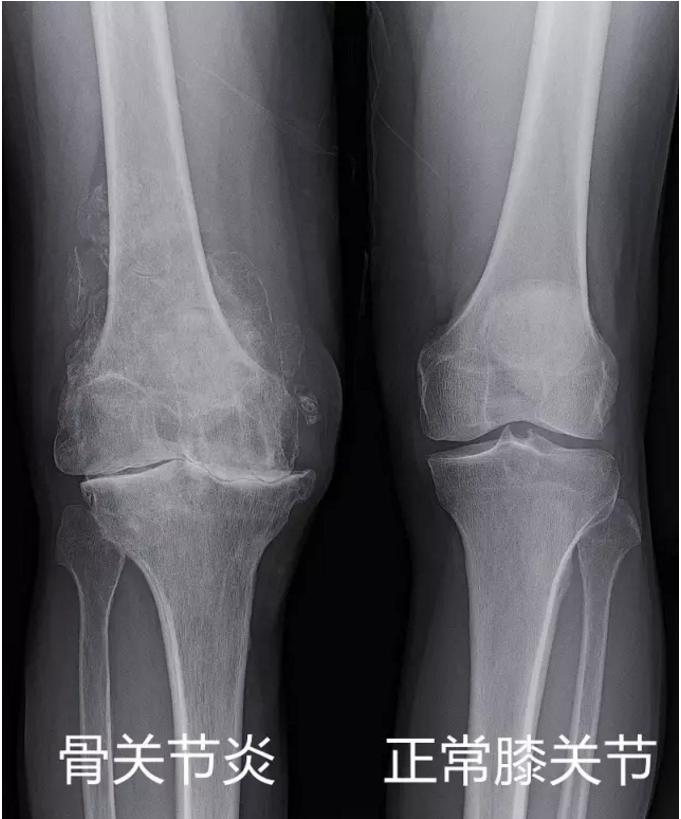

退行性膝骨关节炎是一种发生于老年人的膝关节衰老性病变,临床上以膝关节疼痛,肿胀,僵硬,活动受限为主要症状。主要原因是因为:各种因素导致的,关节内的软骨组织合成与降解失衡,从而导致软骨退化,甚至破坏。从而引发膝关节内的一系列的病理性反应所导致的疾病。

出现这些症状是因为患者膝关节内的软骨发生变性、坏死、剥落,软骨下的骨质发生硬化,骨赘形成,关节内的滑膜充血,绒毛增生等病理改变引发的。